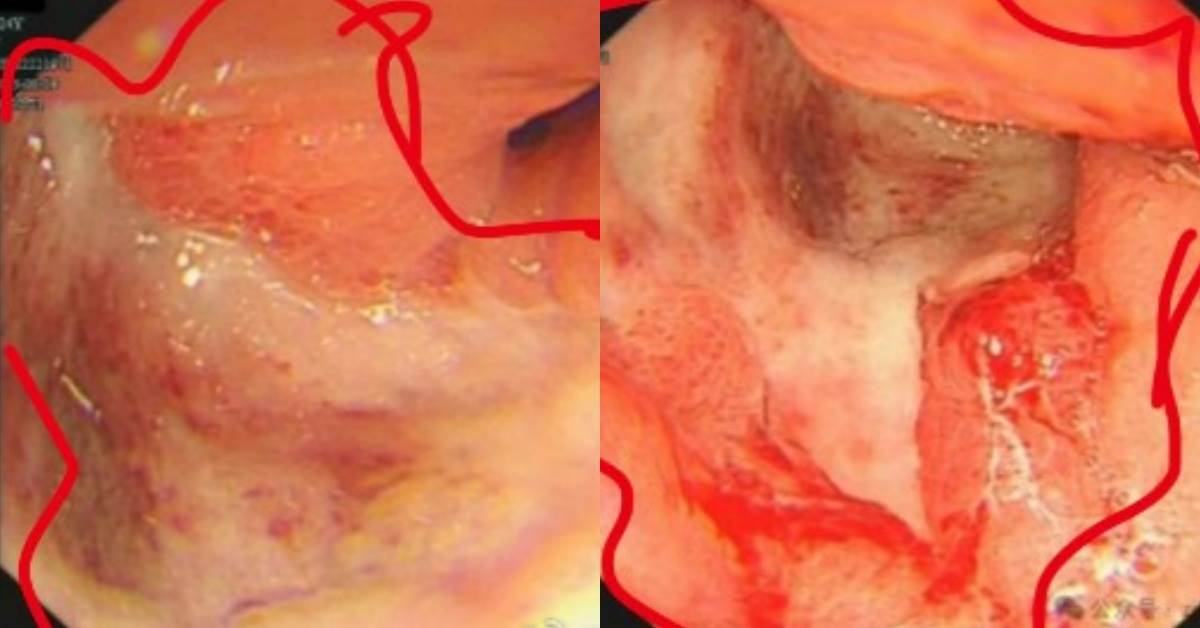

隨著身體狀況逐漸惡化,小雯在拍攝期間多次出現黑便,直到在片場吐血才被送往醫院急診。醫師透過胃鏡檢查後發現,她的胃部被巨大潰瘍占據,胃黏膜僵硬、缺乏彈性,就像「皮革」一樣。

切片檢查後證實,她罹患的是胃癌中惡性程度極高的「印戒細胞癌」;這種癌症因腫瘤細胞充滿黏液、細胞核被擠壓至邊緣,形態酷似戒指而得名,治療難度極高。

小雯(化名)透過院方公開自己的內視鏡圖

圖片來源:微博